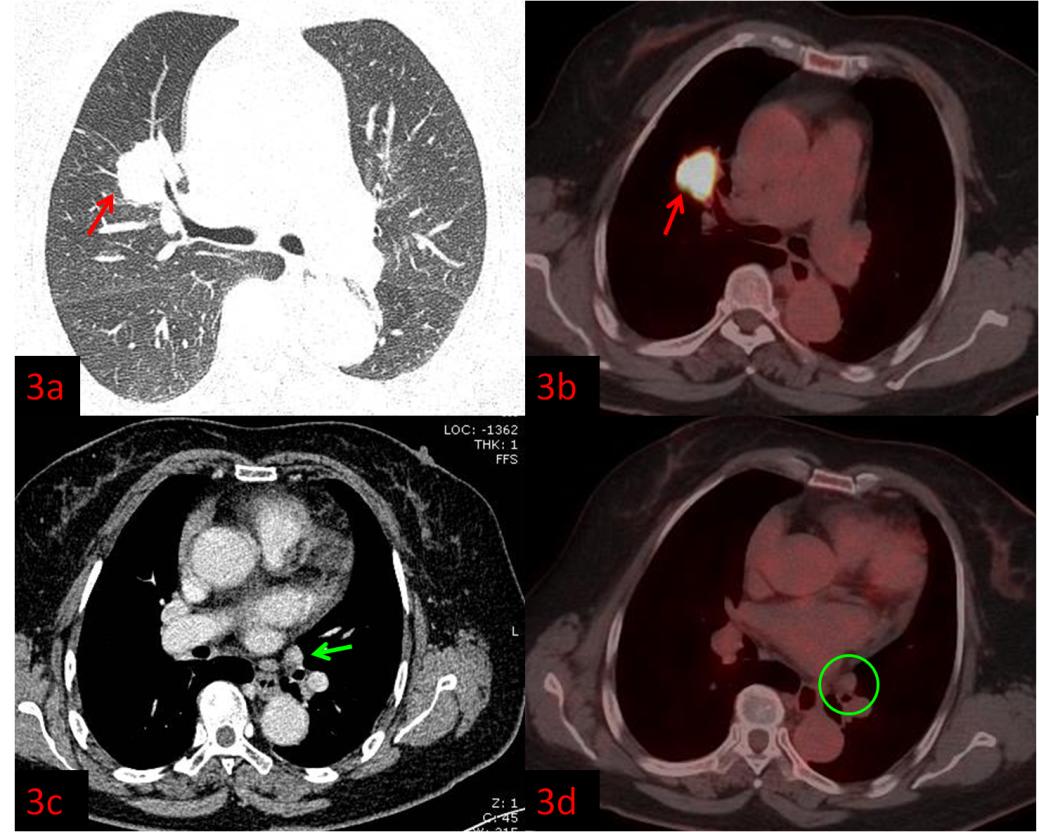

例3:老年女性,右肺上葉病變(紅箭)。強化CT示左肺門腫大淋巴結,轉移不能除外(圖3c綠箭),初步分期為ⅢB,無法行手術根治。而PET/CT顯示淋巴結FDG代謝不高,考慮良性(圖3d綠圈),患者分期降為ⅡB,于是進行了根治性手術。術后病理:右肺腺癌。